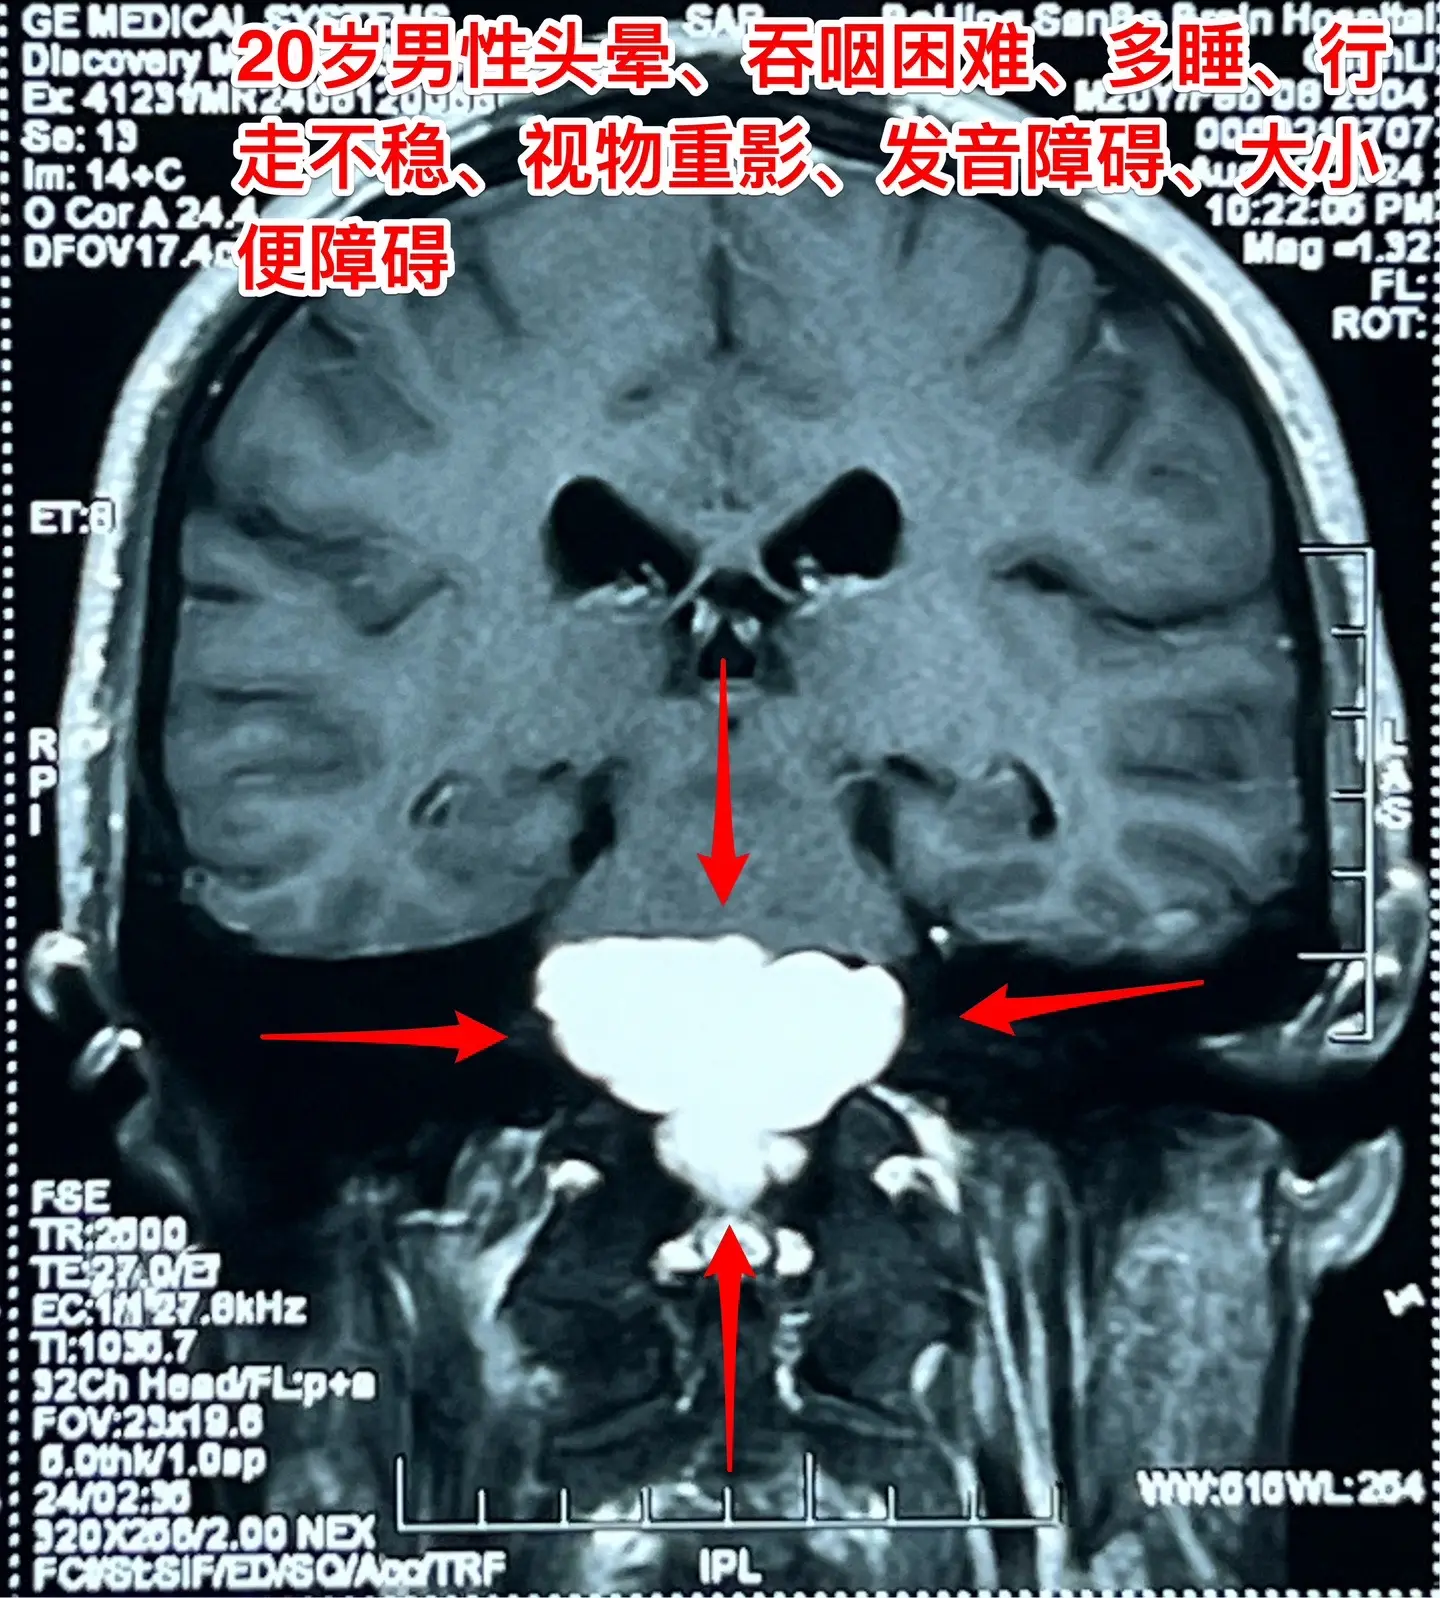

头晕、吞咽困难、行走不稳、大小便障碍。20岁漳州的小伙子,2个月前出现头晕,一个月前出现吞咽困难,半个月个月前出现多睡,一周前出现行走不稳、视物重影、发音不清晰,而且有大小便障碍。 一般人认为这些症状都是七八十岁的老人才会有的,怎么会出现在20岁的年轻人身上呢?他到底得了什么病? 磁共振和CT显示脑干腹侧有一个巨大囊肿,对脑干有明显的压迫,考虑为肠源性囊肿。针对这个病,只有选择作手术切除囊肿,病人的症状才有希望好转。 2024.8.14作了手术,术中看见囊壁与脑干的神经、基底动脉的分支血管粘连。切除大部分囊壁,清除了囊内容物,脑干得到充分减压。 手术后病人的症状显著改善了!